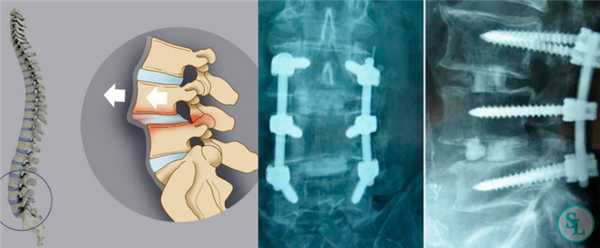

Транспедикулярная фиксация или ТПФ - операция, при которой позвонки фиксируются и стабилизируются при помощи специальных имплантов (транспедикулярных винтов). В каждом позвонке есть точка ввода винта, которую установил в 1985 году Рой Камилл — это точка пересечения поперечного отростка позвонка с верхнем суставным отростком. С помощью специальных инструментов в эту точку, вкручиваются винты определяя анатомически правильное расположение позвоночника, тем самым излечивая заболевание. Первые попытки установки имплантов были в 60-70 гг. прошлого века и с тех пор является «золотым стандартом» в лечения переломов и различных заболеваний позвоночника.

ТПФ выполняется под рентгеновским контролем, что позволяет хирургу точно контролировать каждое движение и избежать повреждения близкорасположенных анатомических структур. Чаще для этого используется ЭОП или КТ.

Очень важно при установки винтов соблюсти следующие моменты: отсутствие пространства между костью и винтом, исключение травматизации нервных и сосудистых структур или смежных дугоотросчатых суставов. Импланты устанавливаются согласно размерной линейки каждого позвонка и винта, бикортикально не касаясь замыкательных пластин.

Точка установки винта в корень дуги подбирается на основании расположения двух анатомических ориентиров - поперечного и суставного отростков позвонка. Непосредственно позвонок перфорируют с помощью специального зонда.